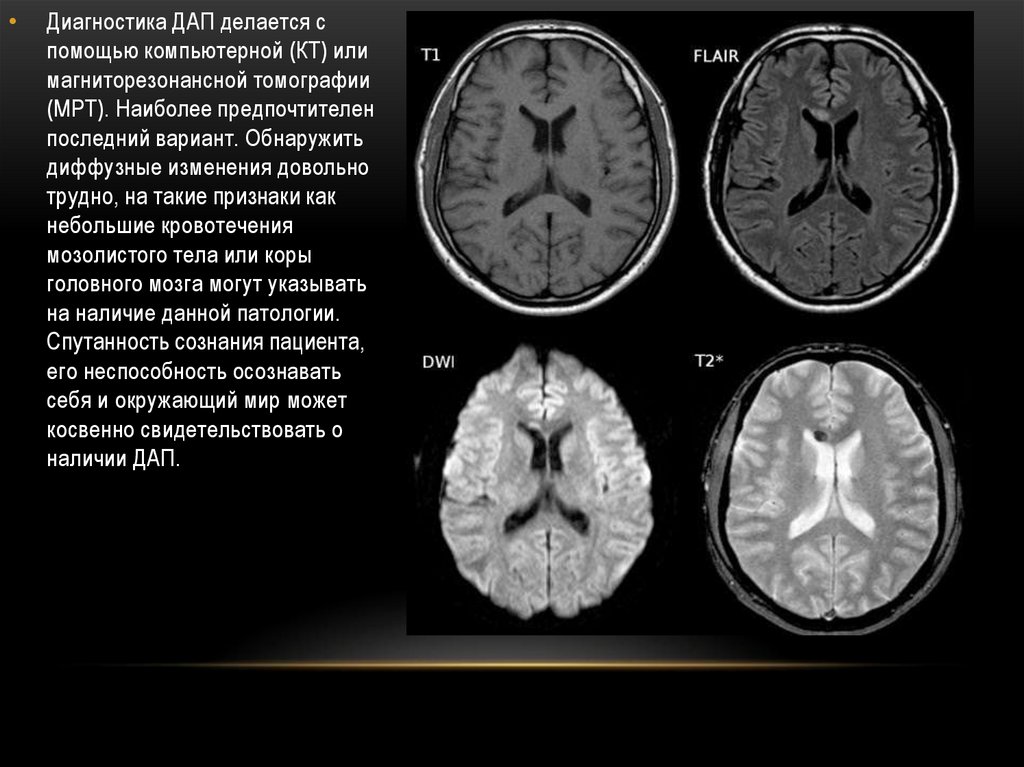

Диагностика ДАП делается с

помощью компьютерной (КТ) или

магниторезонансной томографии

(МРТ). Наиболее предпочтителен

последний вариант. Обнаружить

диффузные изменения довольно

трудно, на такие признаки как

небольшие кровотечения

мозолистого тела или коры

головного мозга могут указывать

на наличие данной патологии.

Спутанность сознания пациента,

его неспособность осознавать

себя и окружающий мир может

косвенно свидетельствовать о

наличии ДАП.